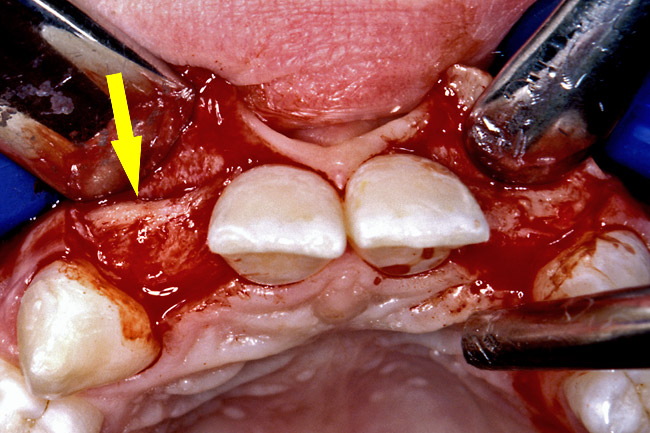

Before the day of surgery, the patient was seen by the orthodontist for the removal of the orthodontic brackets. The patient still was not pleased with the position of the two centrals, and it was determined that this would be addressed after implant placement (Figure 13A). The anatomical variations of the crestal tissue and lack of interdental papilla can be appreciated in the close-up views of the right and left sites (Figure 13B and 13C). There were no surprises on the day of surgery as all of the decisions were made during the planning phase, before the scalpel ever touched the patient. The occlusal view of the CT 3D model revealed the wider alveolar ridge on the right side and thinner crest on the left side (Figure 14A). This was confirmed when the full thickness mucoperiosteal flaps were elevated, and the underyling bone revealed (Figure 14B). The tooth-borne templates were designed to facilitate the drills and drilling sequence specific to the diameters of the predetermined implants (Figure 15A). Each template contained an embedded 5-mm long stainless steel tube, which was approximately 0.2-mm wider than each drill (just wide enough to allow for the drills to rotate freely). Once positioned over the natural teeth, the template was secure and offered precision accuracy in transferring the implant locations from the original software-designed plan, allowing the potential for internal and external irrigation (Figure 15B). The 3.7-mm diameter Tapered Screw-Vent implant drilling sequence requires three drills: pilot, intermediate, and final sizing. Thus, three separate templates were fabricated to a.commodate these sizes. The templates were removed easily and replaced with the next sequential size in less time than it takes to change the drill on the surgical handpiece. After the osteotomies had been.completed, the implants were delivered to the site (Figure 16A and Figure 16B). For this internal hex connection implant, the author r.commends that the flat of the antirotational hex be positioned to the facial for proper orientation of the restorative.components (Figure 17A). Preprepared margins were created from a milled titanium fixture mount transfer post, which was delivered to the implant as support for an immediate transitional restoration. The facial “dot” helped confirm the orientation of the abutment to the facially positioned flat side of the internal hex connection (Figure 17B). Before cementation of the transitional acrylic restorations, a closed-tray, fixture-level impression was made, and a soft-tissue model fabricated.

Figure 14b  The information gained from (A) the 3D model was confirmed when (B) the flaps were elevated.

Figure 14b